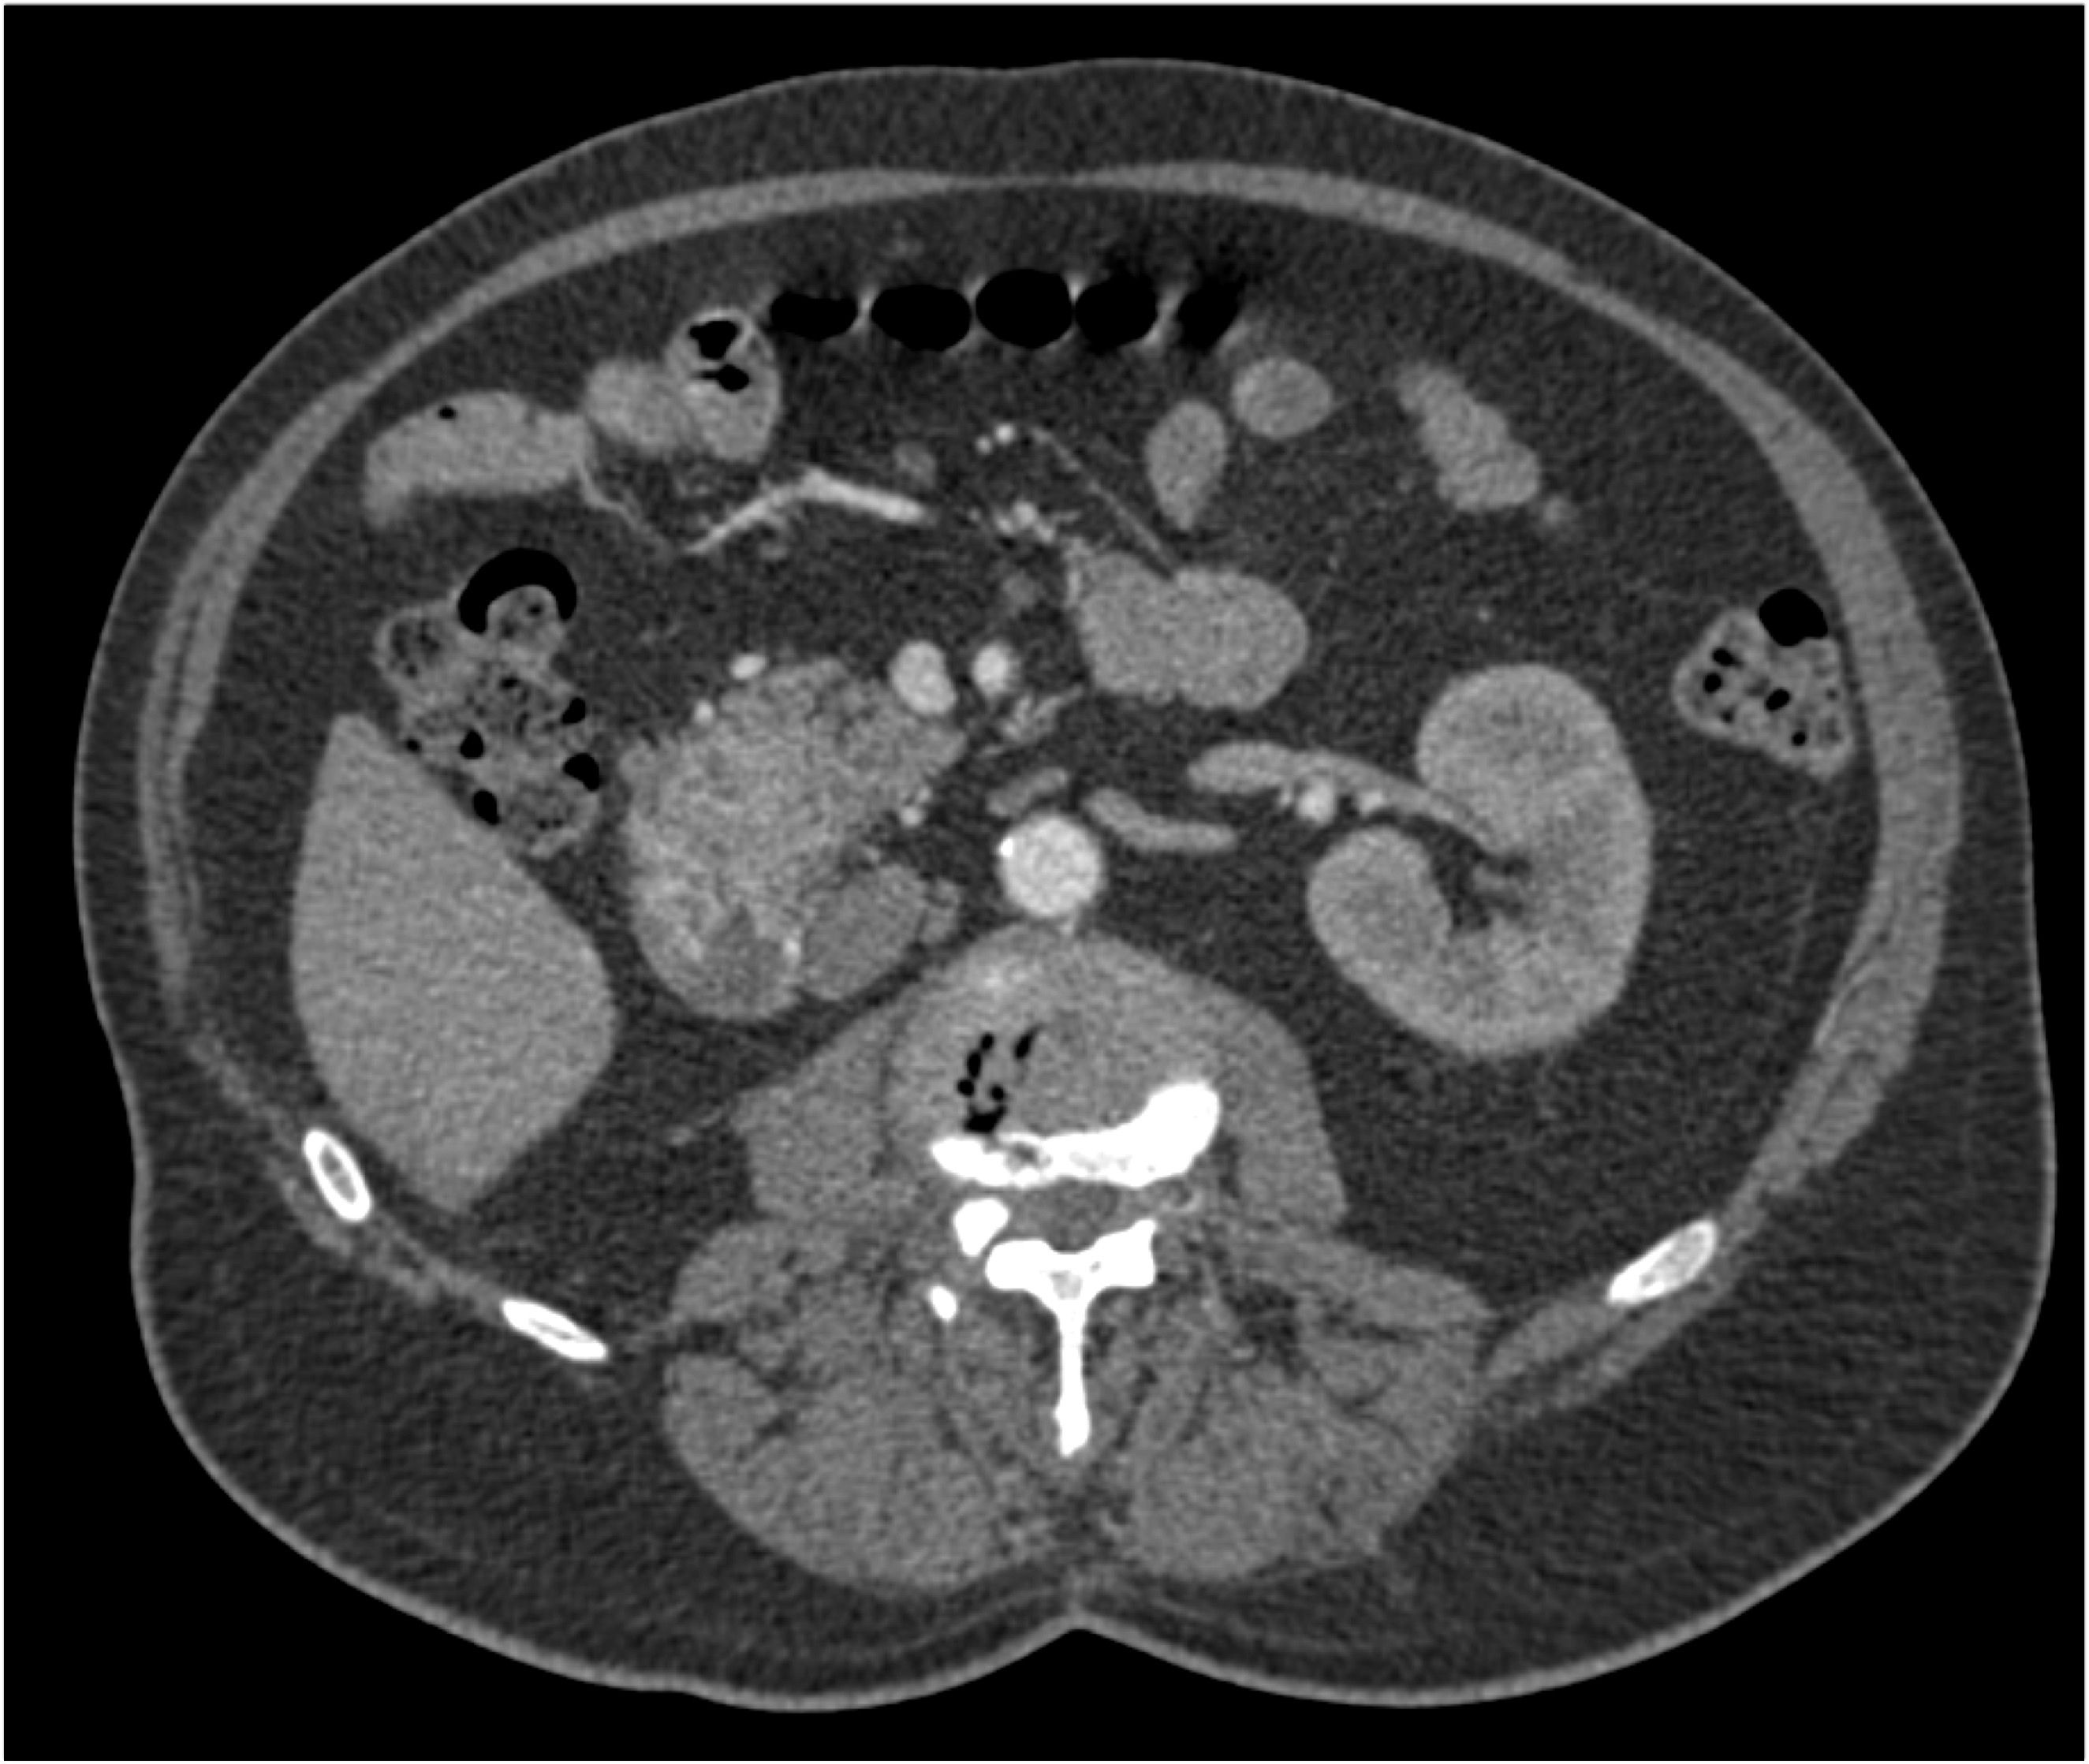

3) The most likely diagnosis in this case is?

adenocarcinoma

GIST tumor

carcinoid tumor

renal cell carcinoma metastatic to duodenum